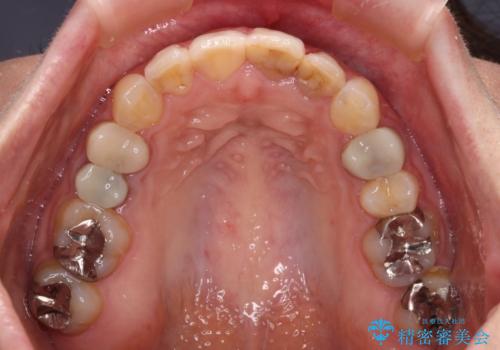

【モニター】前歯のデコボコと奥歯の虫歯 インビザライン治療と奥歯のセラミック治療

矯正治療後半に下顎左右奥歯をセラミッククラウンにて補綴し、その後インビザラインによる歯列の仕上げを行うこととしました。

下顎前歯の叢生が速やかに改善されたため、1年3か月で治療を終えることができました。

下顎前歯は後戻りを起こしやすいため、舌側を細いワイヤーで固定することで後戻り対策を行っています。